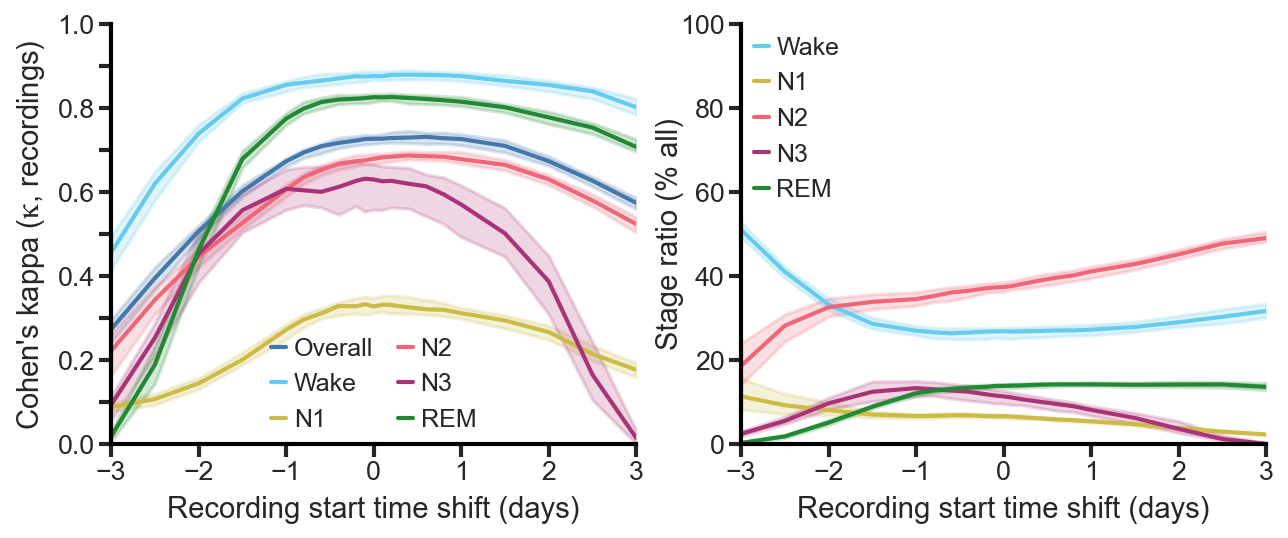

2015 SfN (k=0.280)

I gave my first talk at the 2015 Society for Neuroscience’s (SfN) annual meeting in Chicago. At the time, I was using combinations of “traditional” machine learning techniques on tons of hand-crafted features (from the RR itself, the spectrum of the RR, etc.), but the results were not great. The Cohen’s kappa was 0.28—pretty abysmal. I also presented a new parametric non-sinusoidal function that I found better matched the RR intervals during respiratory sinus arrhythmia (RSA) than a simple sine wave.

2017 SfN (k=0.530)

I presented these findings at the 2017 SfN meeting in D.C. on a “dynamic” poster (i.e., a large TV). The results were now a quite respectable Cohen’s kappa of 0.530—better than state-of-the-art on 5-stage scoring for “EEG-less” methods (any method for sleep staging that makes no use of brain, i.e., EEG data). For reference, the current state-of-the-art on 5-stage scoring was k=0.510 from Sady et al, 2013 [1].

2018 SfN (k=0.710)

I gave my second talk at the 2018 SfN meeting in San Diego, where I demonstrated that we had reached a Cohen’s kappa of 0.710 on 5-stage scoring. We were now significantly better than state-of-the-art, and finally within the range of expert human-scored PSG.

In 2020 a new, published, state-of-the-art threshold was reached for EEG-less methods, k=0.585 from Sun et al. [2]. However, unbeknownst to anyone that didn’t attend my 2018 SfN talk, this was significantly below the k=0.710 I had already presented.

2024 CIBM (k=0.725)

To address the biggest concern from the initial round of reviews, I taught myself about meta-analyses and non-inferiority testing. And, after another two rounds of reviews, the paper was accepted by CIBM on April 28th.